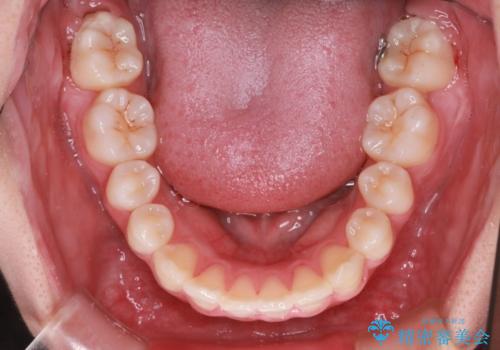

- 前歯の叢生と突出感を主訴に来院されました。

抜歯をしてワイヤー矯正を行いました。

上顎両側小臼歯を抜歯して治療を行い、突出感も大幅に改善しました。